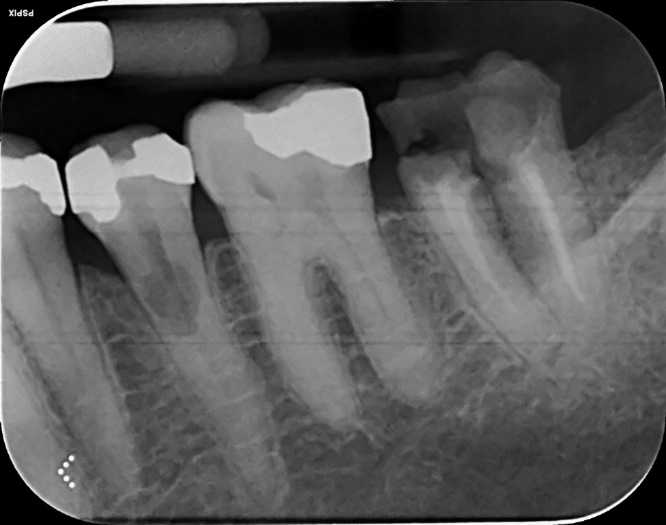

Lower Molar Primary root canal treatment